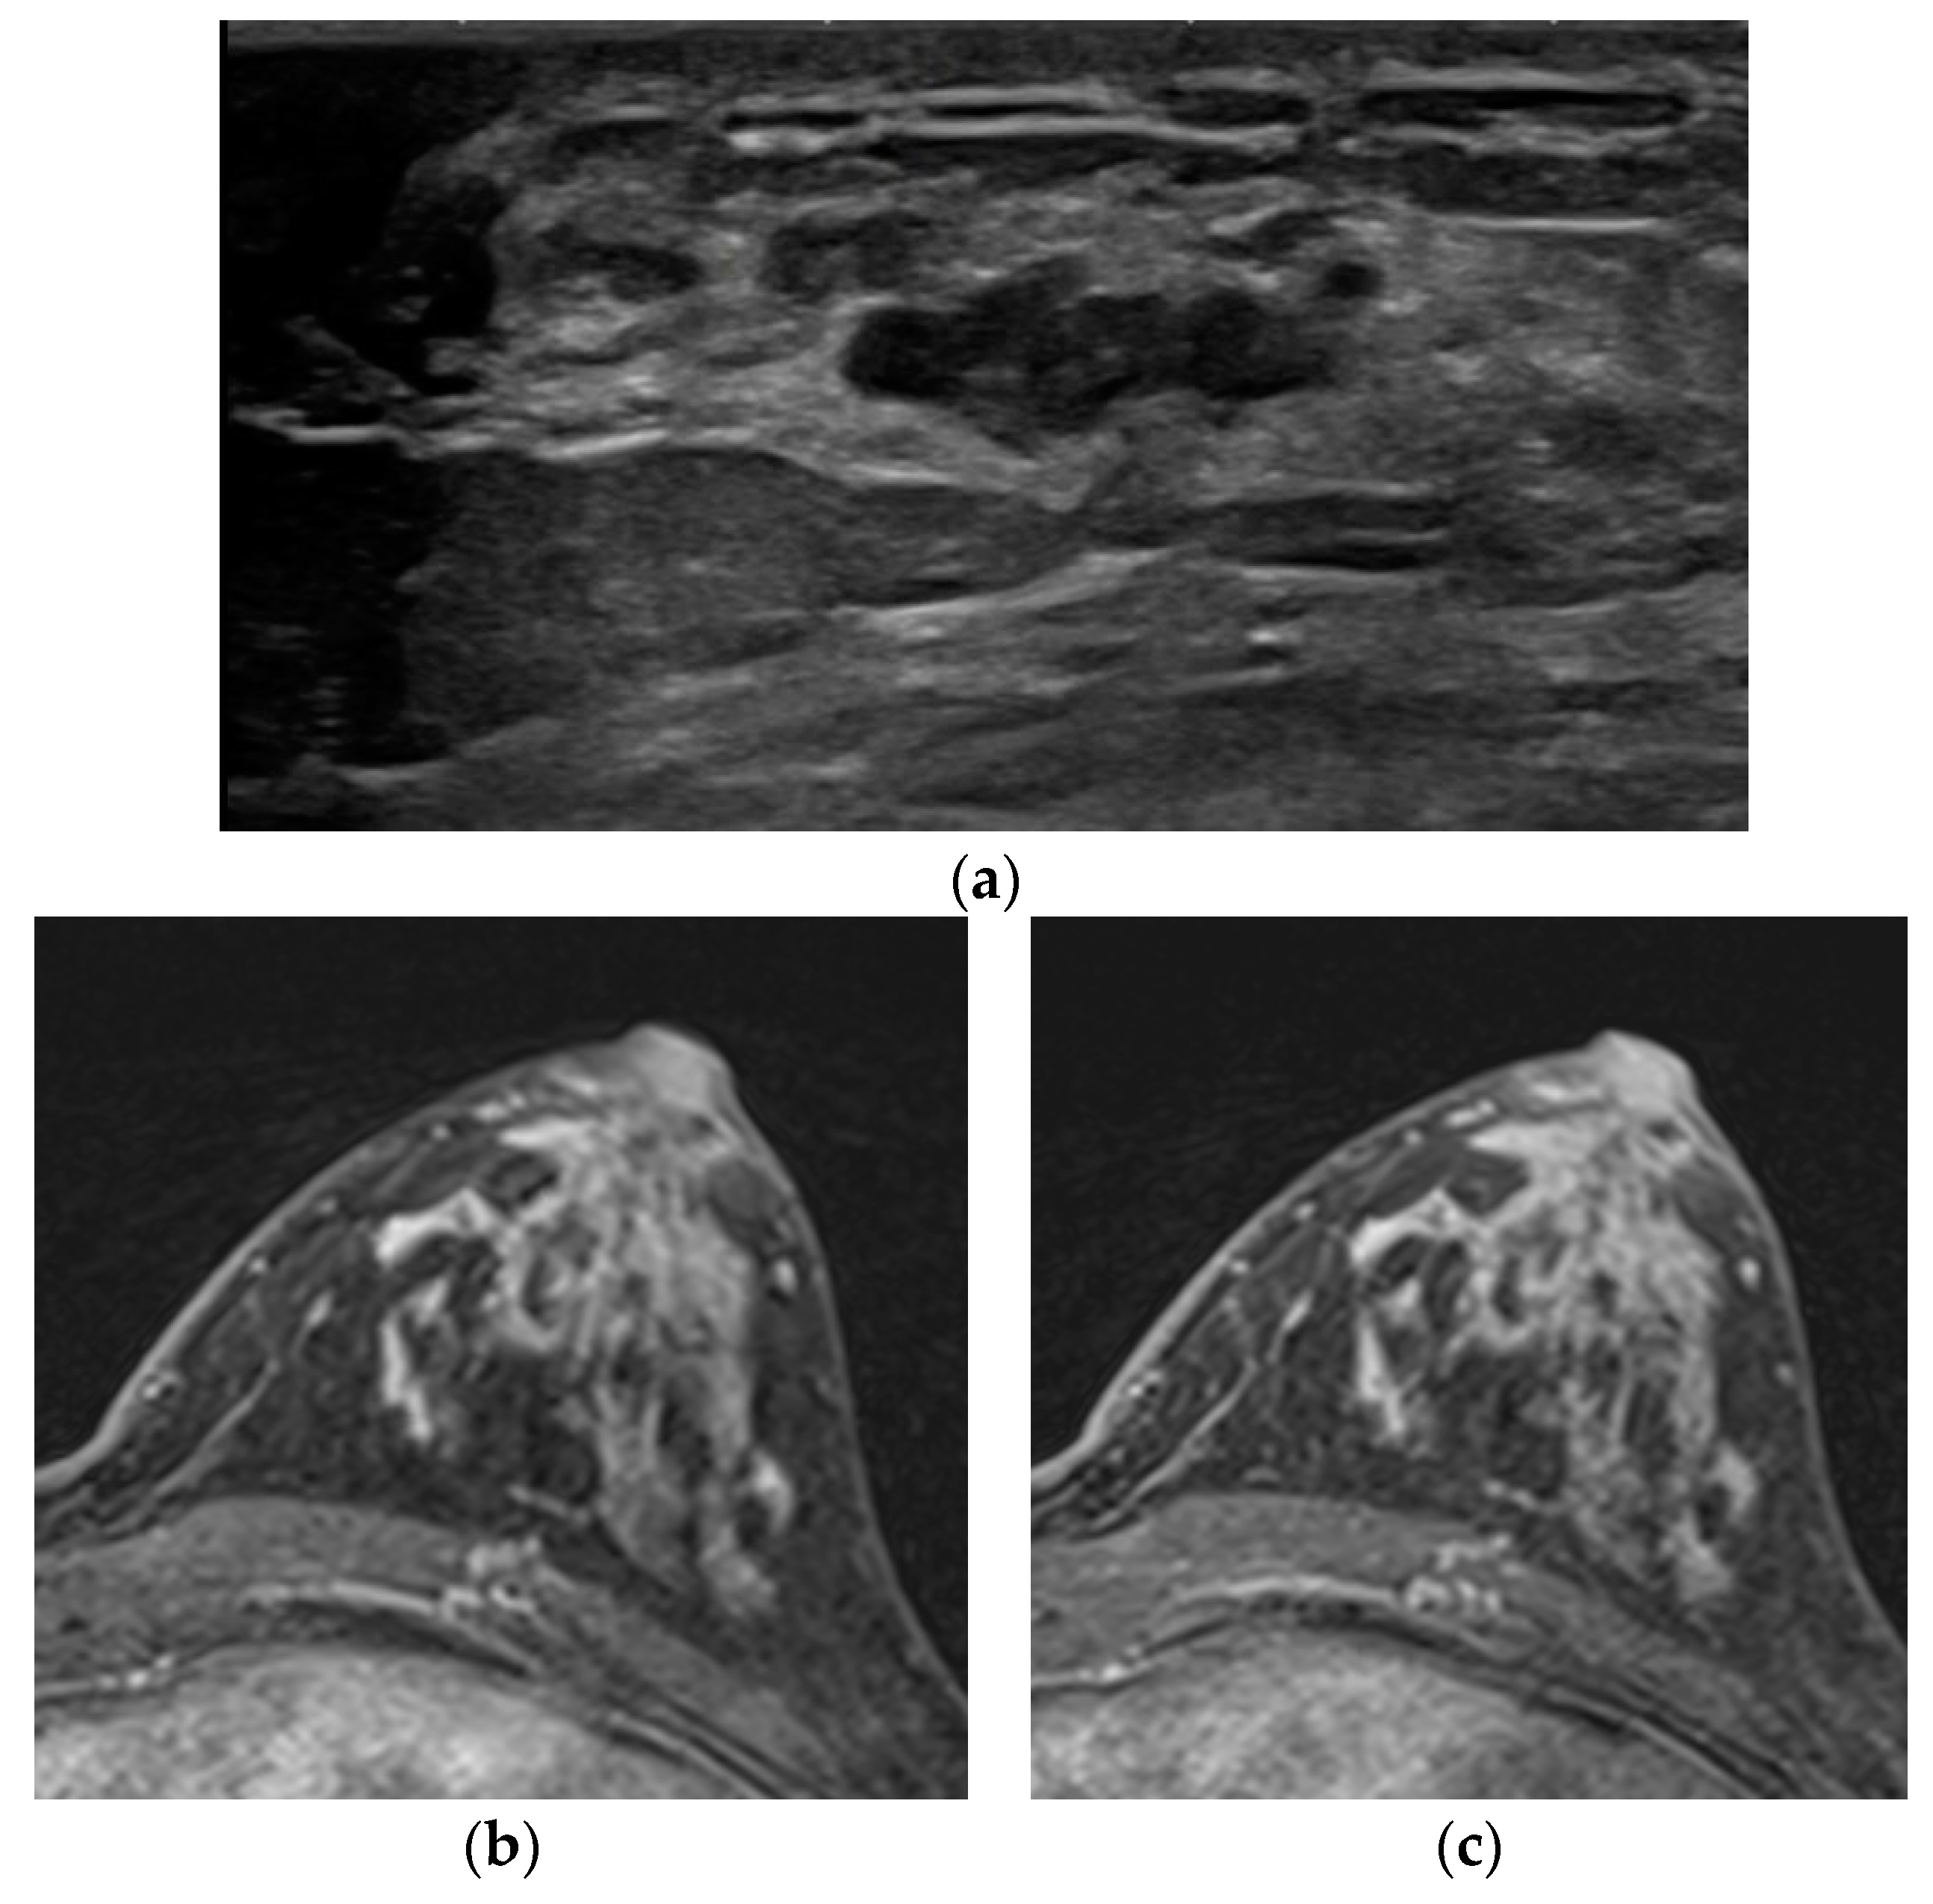

| 10 | 62 | ILC | 20 | Rt 1-o’ clock | marked | BPE | - | - | Focal asymmetry | Mass |

| 11 | 53 | IDC | 5 | Lt 3-o’ clock | marked | BPE | - | - | - | Mass |

| 12 | 36 | DCIS | 45 | Lt 12-o’ clock | marked | BPE | - | - | Microcalcifications | - |